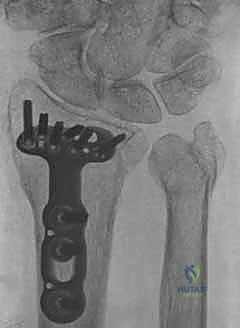

2. كسور رأس الزند (Ulnar Head Fractures)

رأس الزند هو الجزء المفصلي الدائري الذي يدور حوله الكعبرة.

* كسور مفصلية (Articular Fractures): تمتد خطوط الكسر لتشمل الغضروف المفصلي. إذا لم يتم إعادة العظام إلى وضعها التشريحي المثالي (Anatomic Reduction)، فإن المريض سيكون عرضة للإصابة بخشونة المفاصل المبكرة (Post-traumatic Osteoarthritis) وفقدان القدرة على تدوير الساعد.

* كسور غير مفصلية: تقع تحت السطح المفصلي مباشرة، ولكنها قد تؤدي إلى تشوه في زاوية رأس الزند.

ثانياً: العلاج الجراحي (Surgical Intervention)

متى يقرر الدكتور هطيف ضرورة التدخل الجراحي؟

1. عدم الاستقرار (Instability): إذا كان المفصل الزندي الكعبري البعيد (DRUJ) غير مستقر بعد تثبيت كسر الكعبرة.

2. الانزياح (Displacement): إذا كان الكسر في قاعدة الناتئ الإبري منزاحًا بأكثر من 2 ملم.

3. الكسور المفصلية: أي كسر يخل بتطابق السطح المفصلي لرأس الزند.

4. الكسور المفتتة: في الجزء الكردوسي التي تؤدي إلى قصر عظم الزند.

5. الكسور المفتوحة (Open Fractures): حيث يبرز العظم من الجلد، وتتطلب جراحة طارئة لتنظيف الجرح وتثبيت الكسر لمنع العدوى.

خطوات التدخل الجراحي الدقيق مع الأستاذ الدكتور محمد هطيف

تُعد جراحات المعصم والزند من الجراحات الدقيقة التي تتطلب مهارة عالية، وهو المجال الذي يتفوق فيه الأستاذ الدكتور محمد هطيف بفضل استخدامه لتقنيات الجراحة المجهرية (Microsurgery) والأدوات الجراحية ذات التقنية العالية.

1. التخطيط ما قبل الجراحة (Pre-operative Planning)

يقوم الدكتور هطيف بدراسة الأشعة المقطعية ثلاثية الأبعاد بدقة، ويختار نوع وحجم الصفائح المعدنية (Plates) والمسامير (Screws) المناسبة لكل مريض بناءً على حجم العظم ونوع الكسر.